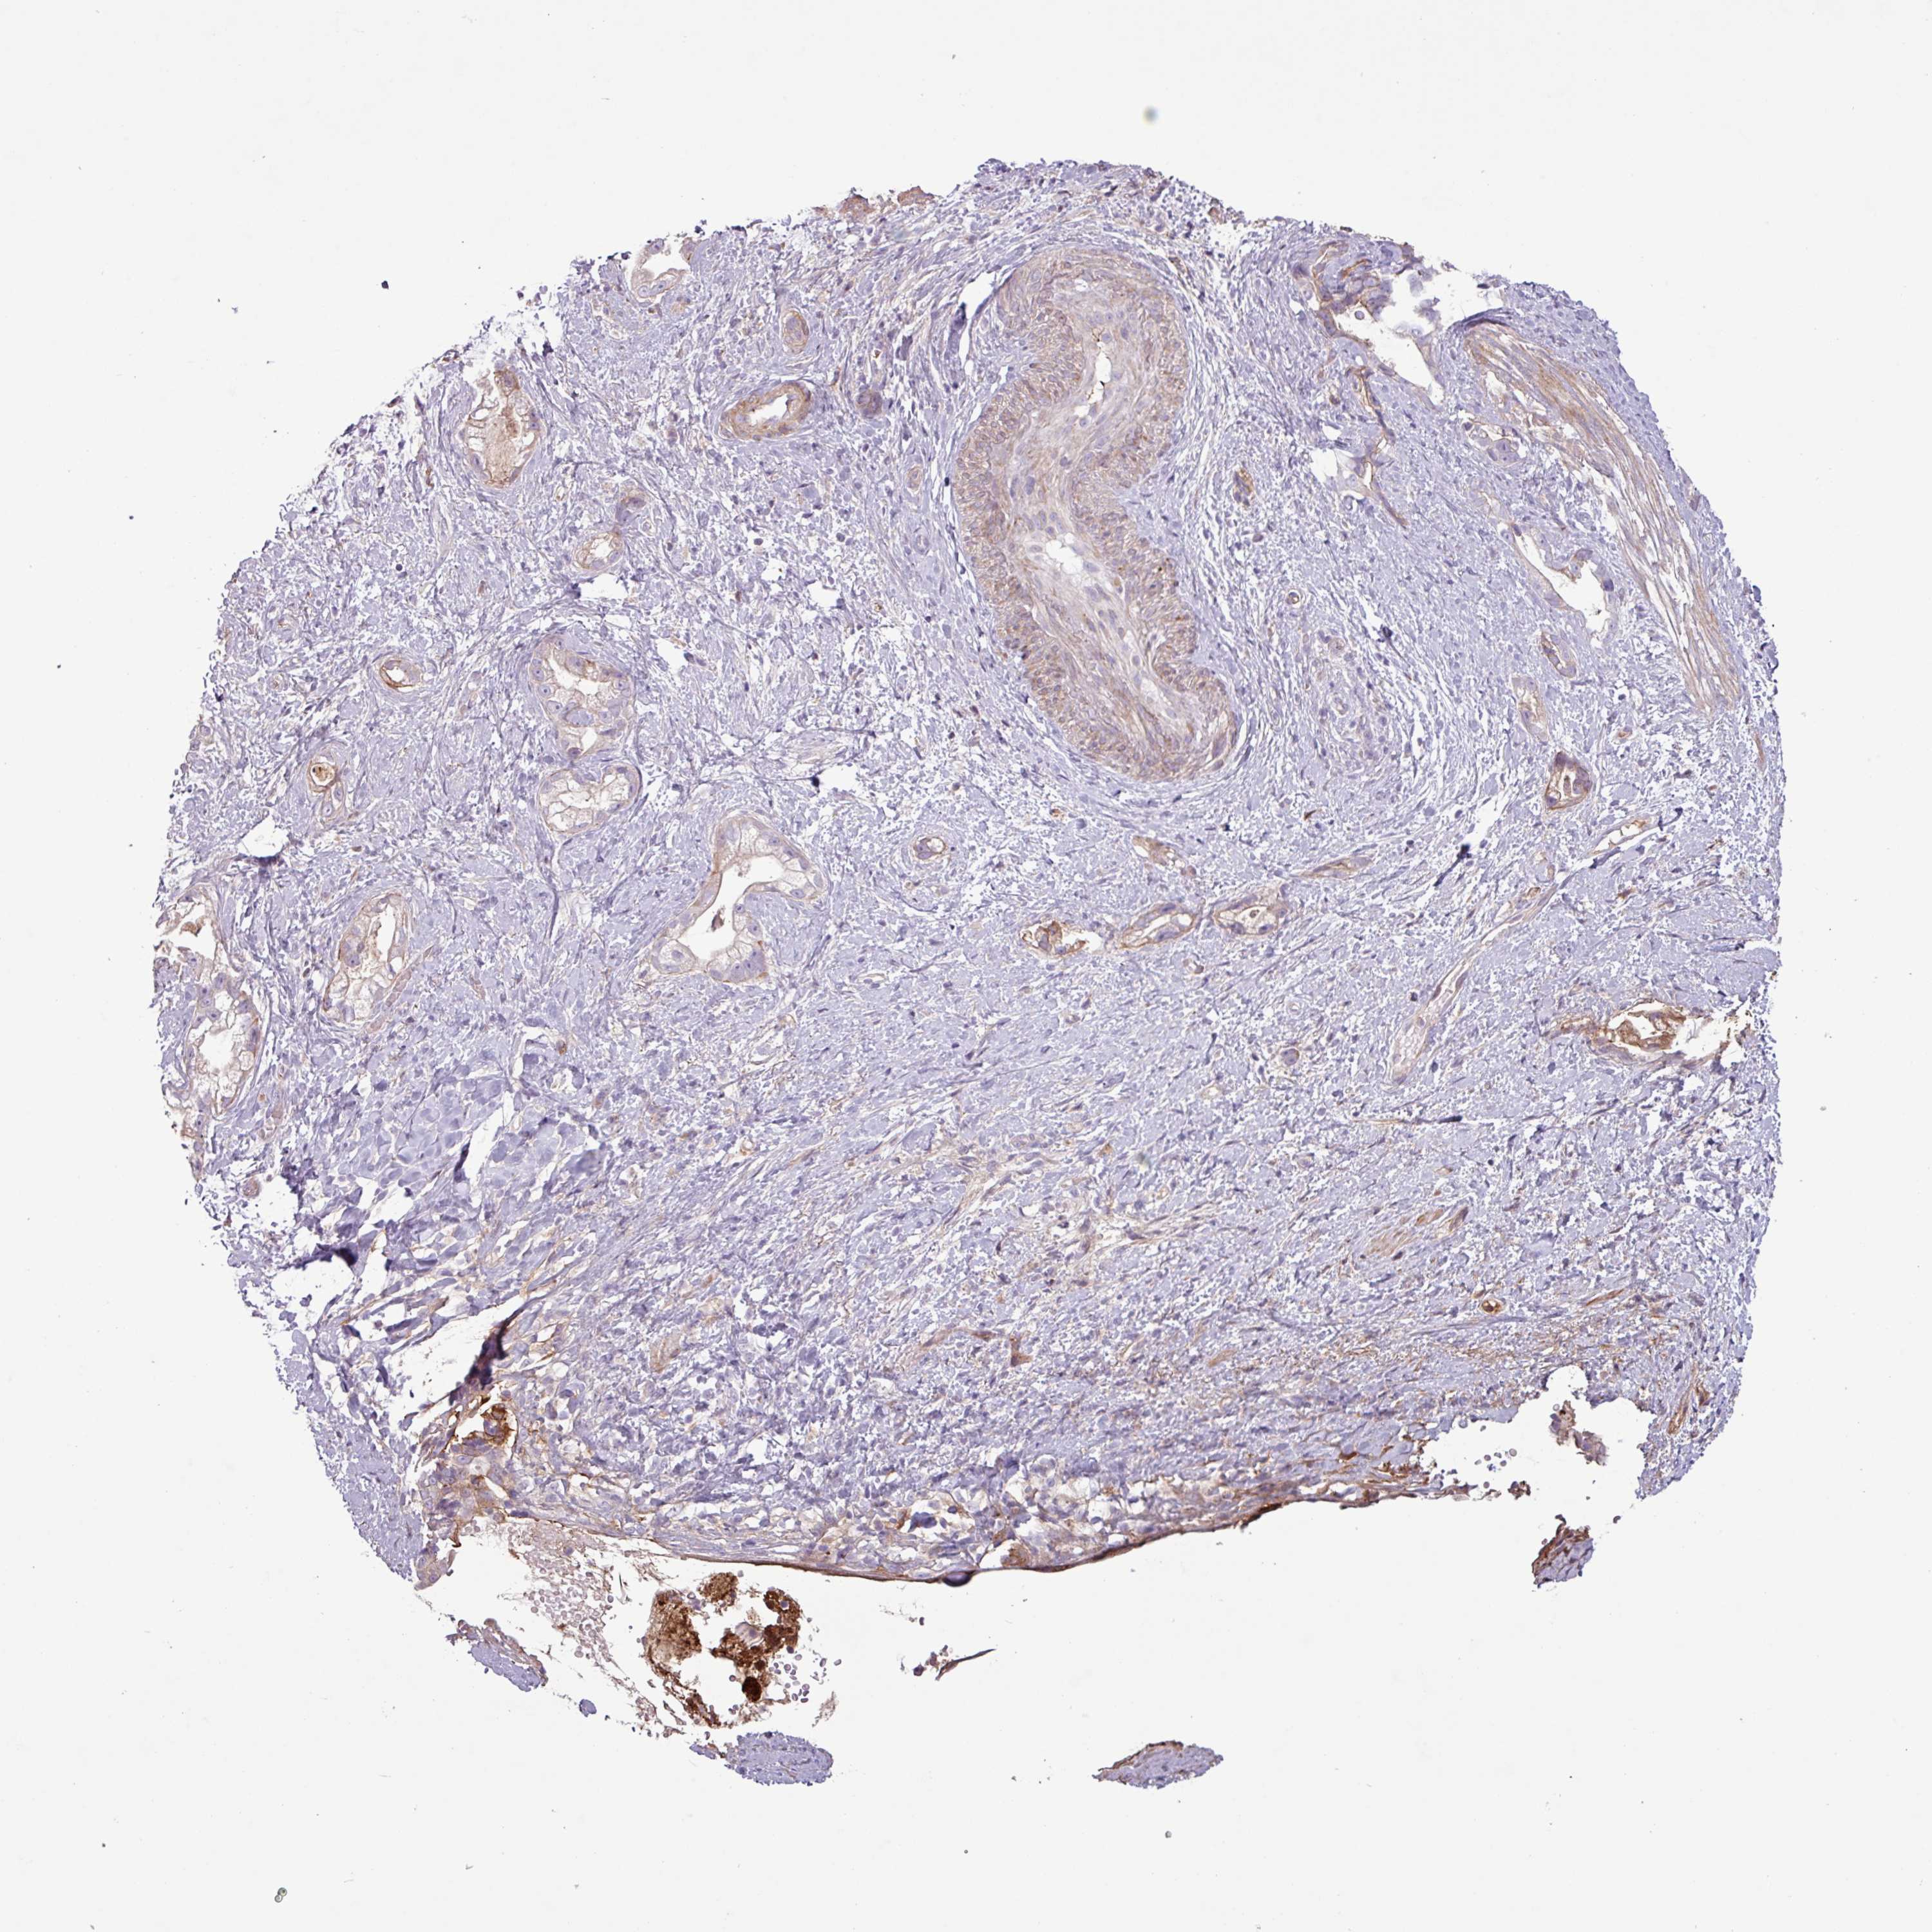

STOMACH CANCER - Protein expressioni

A mouse-over function shows sample information and annotation data. Click on an image to view it in a full screen mode. Samples can be filtered based on level of antibody staining by selecting one or several of the following categories: high, medium, low and not detected. The assay and annotation is described here.

Note that samples used for immunohistochemistry by the Human Protein Atlas do not correspond to samples in the TCGA dataset.

Antibody stainingi

Antibody staining in the annotated cell types in the current human tissue is reported as not detected, low, medium, or high, based on conventional immunohistochemistry profiling in selected tissues. This score is based on the combination of the staining intensity and fraction of stained cells.

Each image is clickable and will lead to virtual microscopy that enables deeper exploration of all samples and also displays staining intensity scores, fraction scores and subcellular localization as well as patient and tissue information for each sample.

Staining

High

Medium

Low

Not detected

Intensity

Strong

Moderate

Weak

Negative

Quantity

>75%

75%-25%

<25%

None

Location

Nuclear

Cytoplasmic/membranous

Cytoplasmic/membranous,nuclear

Adenocarcinoma, NOS